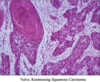

what does cervical cancer look like histologically?

invasive squamous carcinoma - virus integrated into host DNA

75-95% of malignant cervical tumours are what kind?

invasive squamous carcinoma (2nd most common female cancer worldwide)

*develops from CIN - preventable by screening